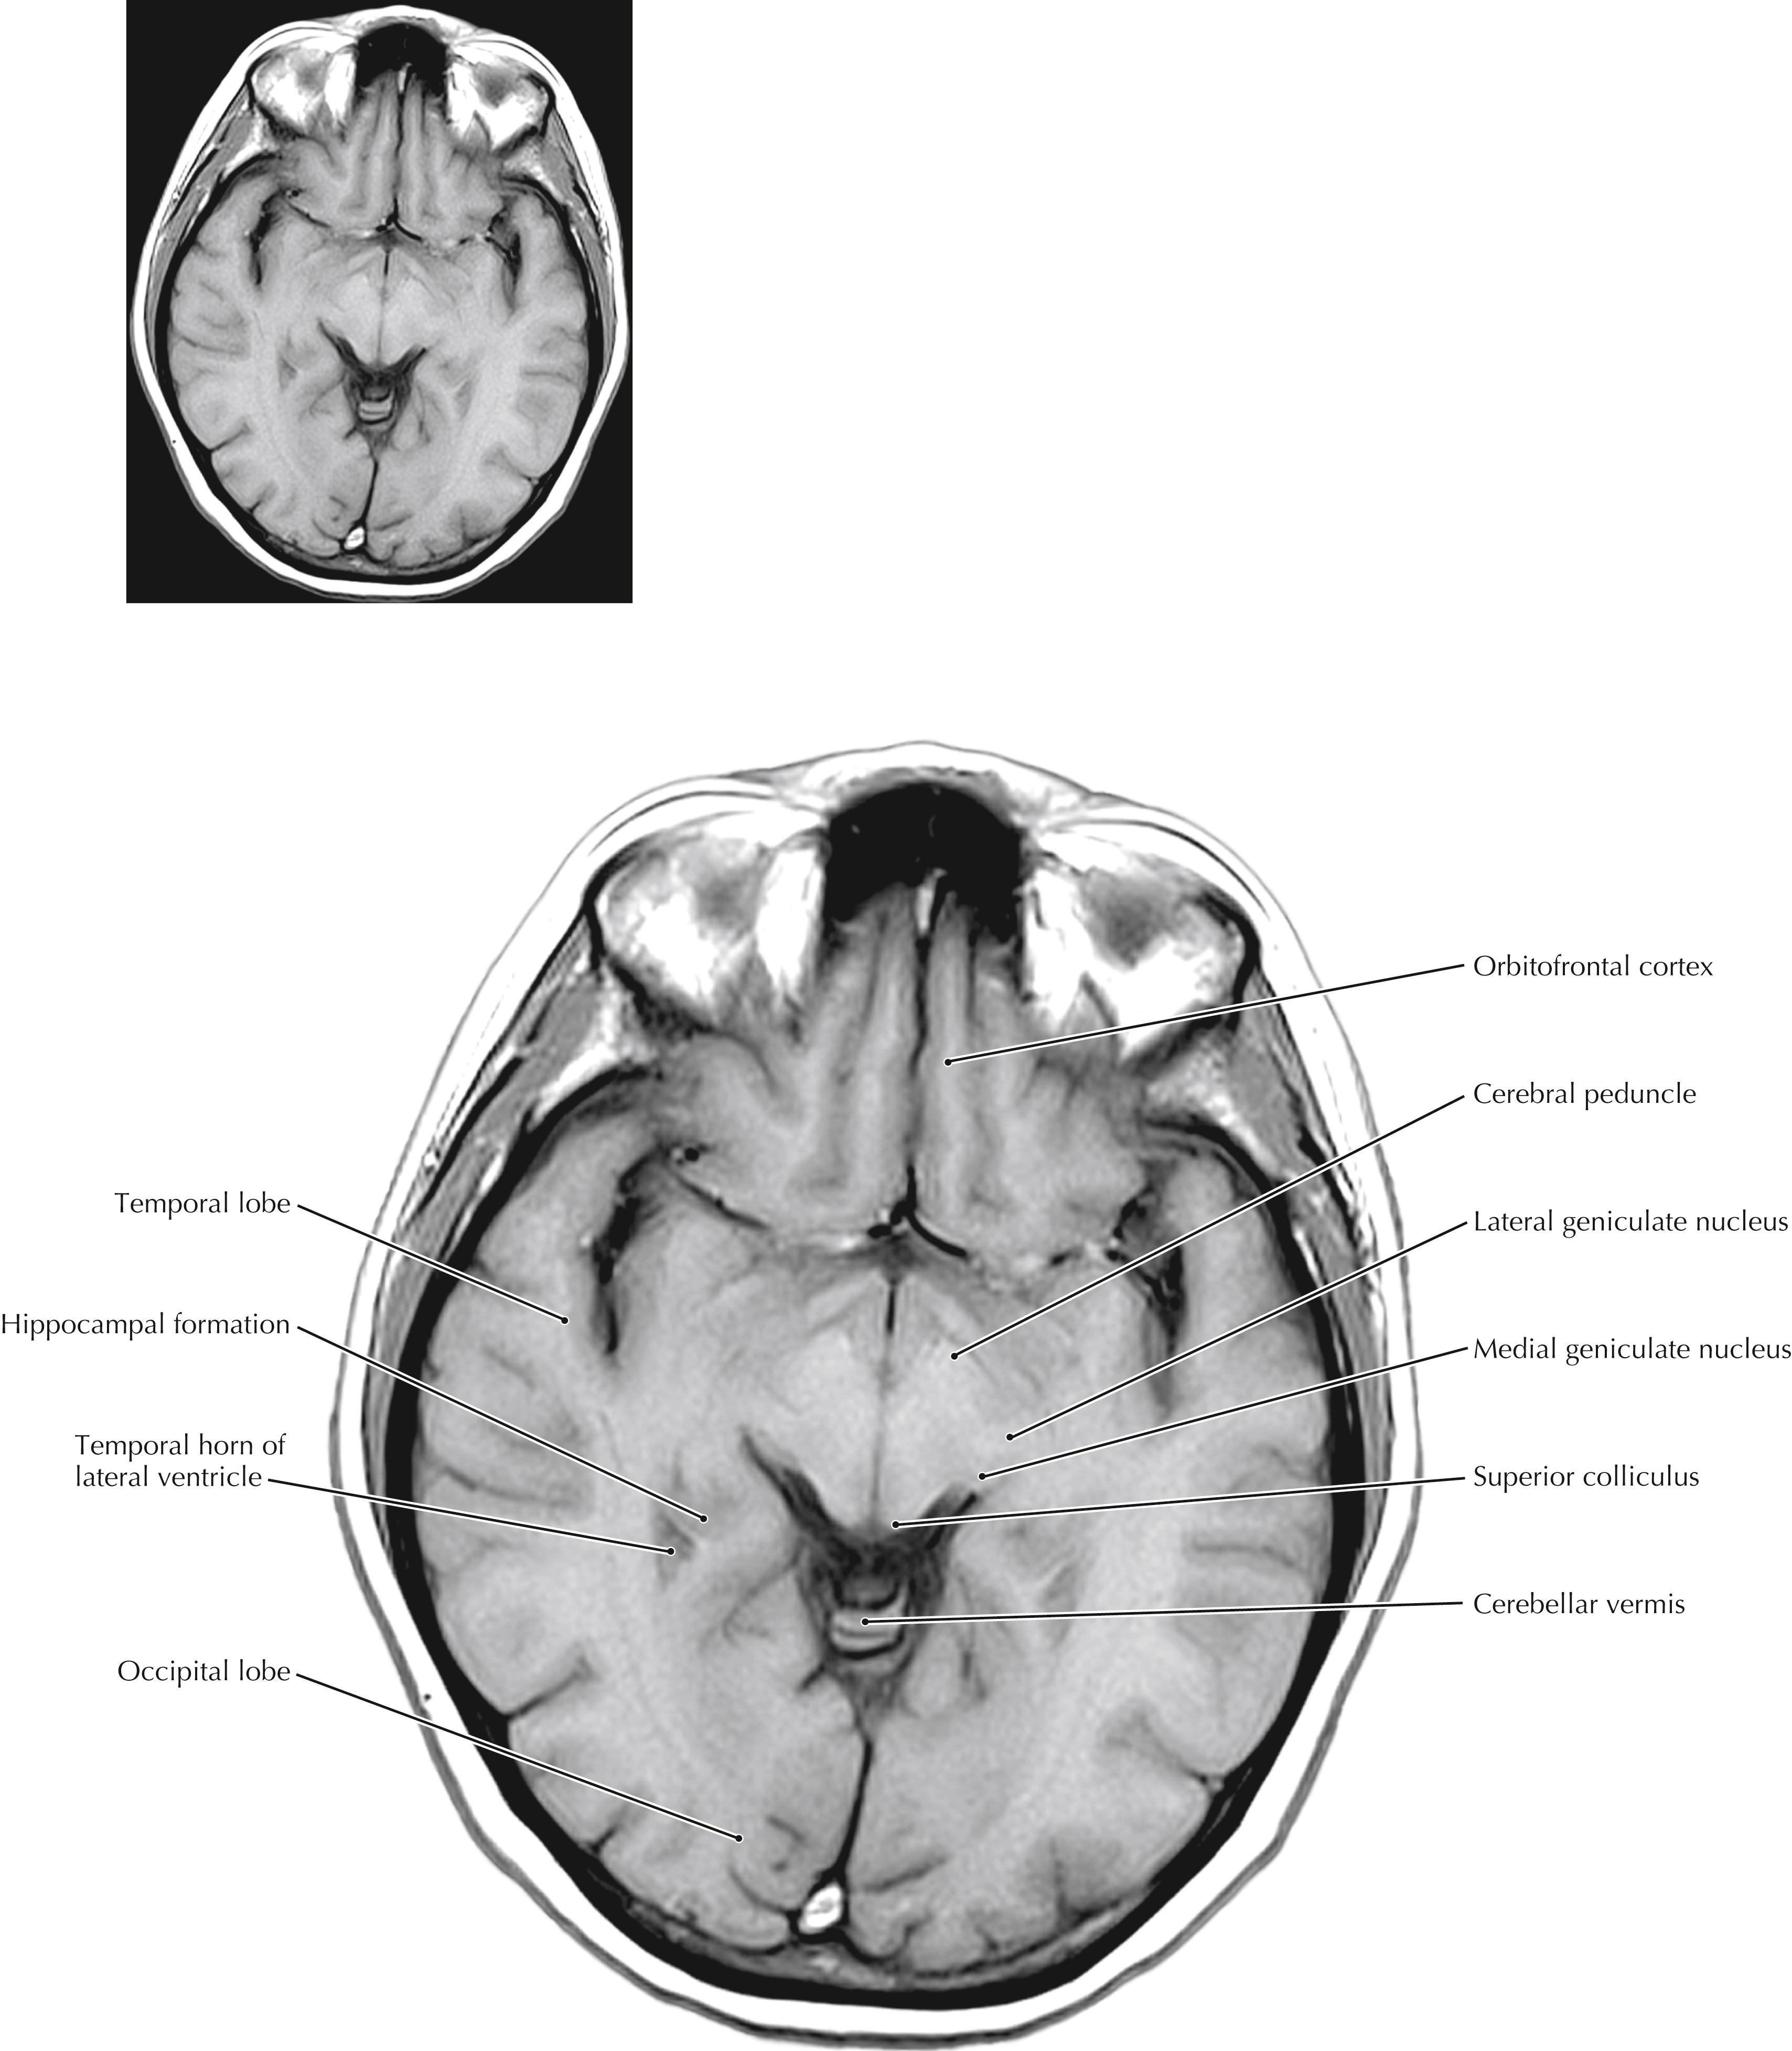

These axial (horizontal) sections compare anatomical sections and high-resolution magnetic resonance (MR) images. They are cut in the true horizontal (axial) plane, not in the older 25-degree tilt. The most important anatomical relationships in these sections center on the internal capsule (IC). The head of the caudate nucleus is medial to the anterior limb of the IC and forms the lateral margin of the frontal pole of the lateral ventricle. The thalamus is medial to the posterior limb of the IC. The globus pallidus and putamen are lateral to the wedge-shaped IC. The posterior limb of the IC carries the major descending corticospinal, corticorubral, and corticoreticular fibers and the ascending sensory fibers of the somatosensory and trigeminal systems. The most posterior portions of the posterior limb also carry the auditory and visual projections to their respective cortices. The genu of the IC carries the corticobulbar fibers. The anterior limb of the IC carries cortical projections to the striatum and the pontine nuclei (pontocerebellar system). The full-plate MR images are T1-weighted; the ventricles appear dark. The scout MR images that accompany the drawings are T2-weighted MR images, in which the cerebrospinal fluid (CSF) appears white.

Axial (Horizontal) Sections Through the Forebrain: Level 3—Midbrain